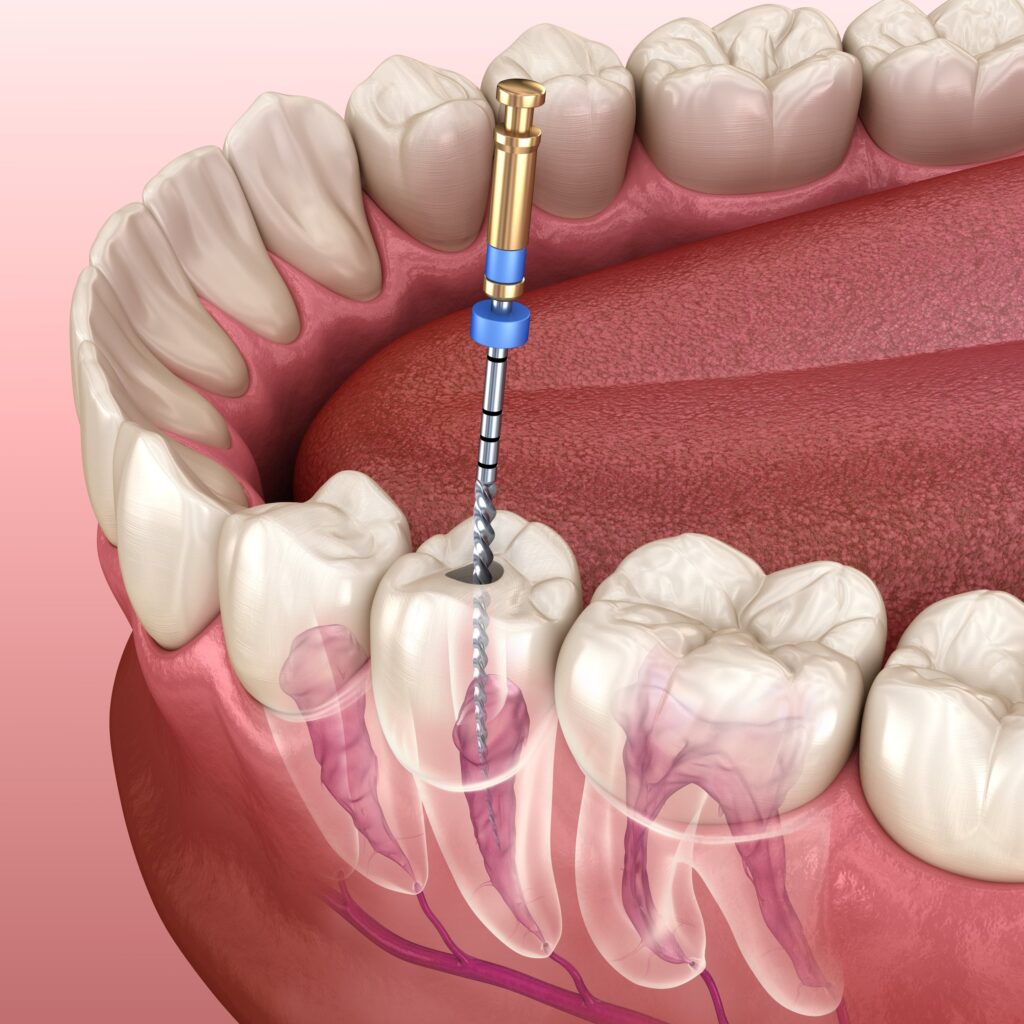

QUY TRÌNH CẮT CHÓP Răng

- 3. Gây tê, tiếp cận và cắt chóp chân răng: Trước khi bắt đầu quy trình, vùng cần điều trị sẽ được gây tê để đảm bảo bạn không cảm thấy đau hoặc khó chịu trong suốt quá trình điều trị. Bác sĩ sẽ tạo đường vào vị trí chóp răng bị nhiễm trùng, loại bỏ khoảng 2mm phần chóp răng, đồng thời làm sạch mô viêm xung quanh.